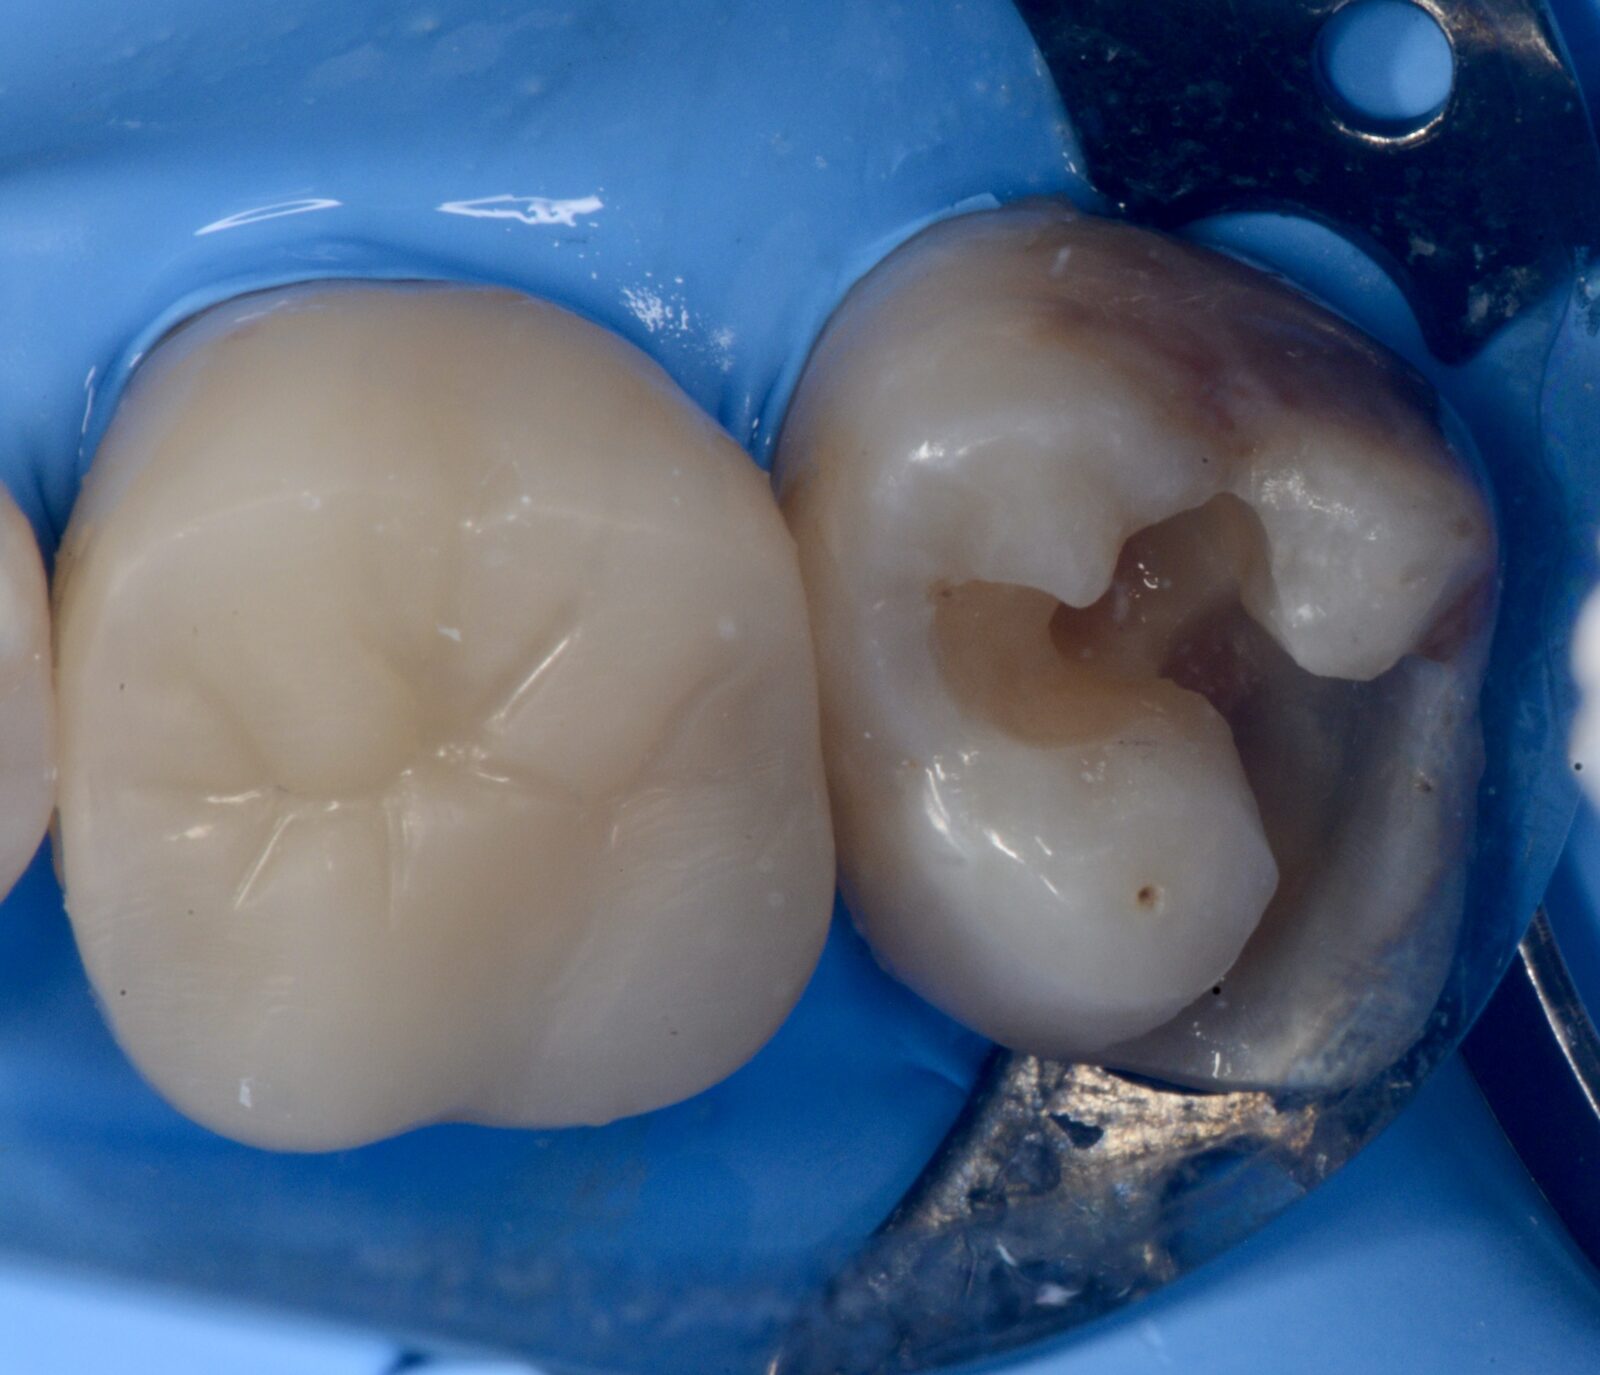

治療前 治療後

左上6,7ダイレクトボンディング

左上6➡他院で治療したセラミックスの接着不良からの二次感染。 左上7➡コンポジットレジンの接着不良からの二次感染。   ともに、旧充填物と感染歯質を除去後、歯面処理と接着操作を行う。 その後、ダイレクトボンディングにて、充填処置を行い、ティント(ブラウンとホワイト)…